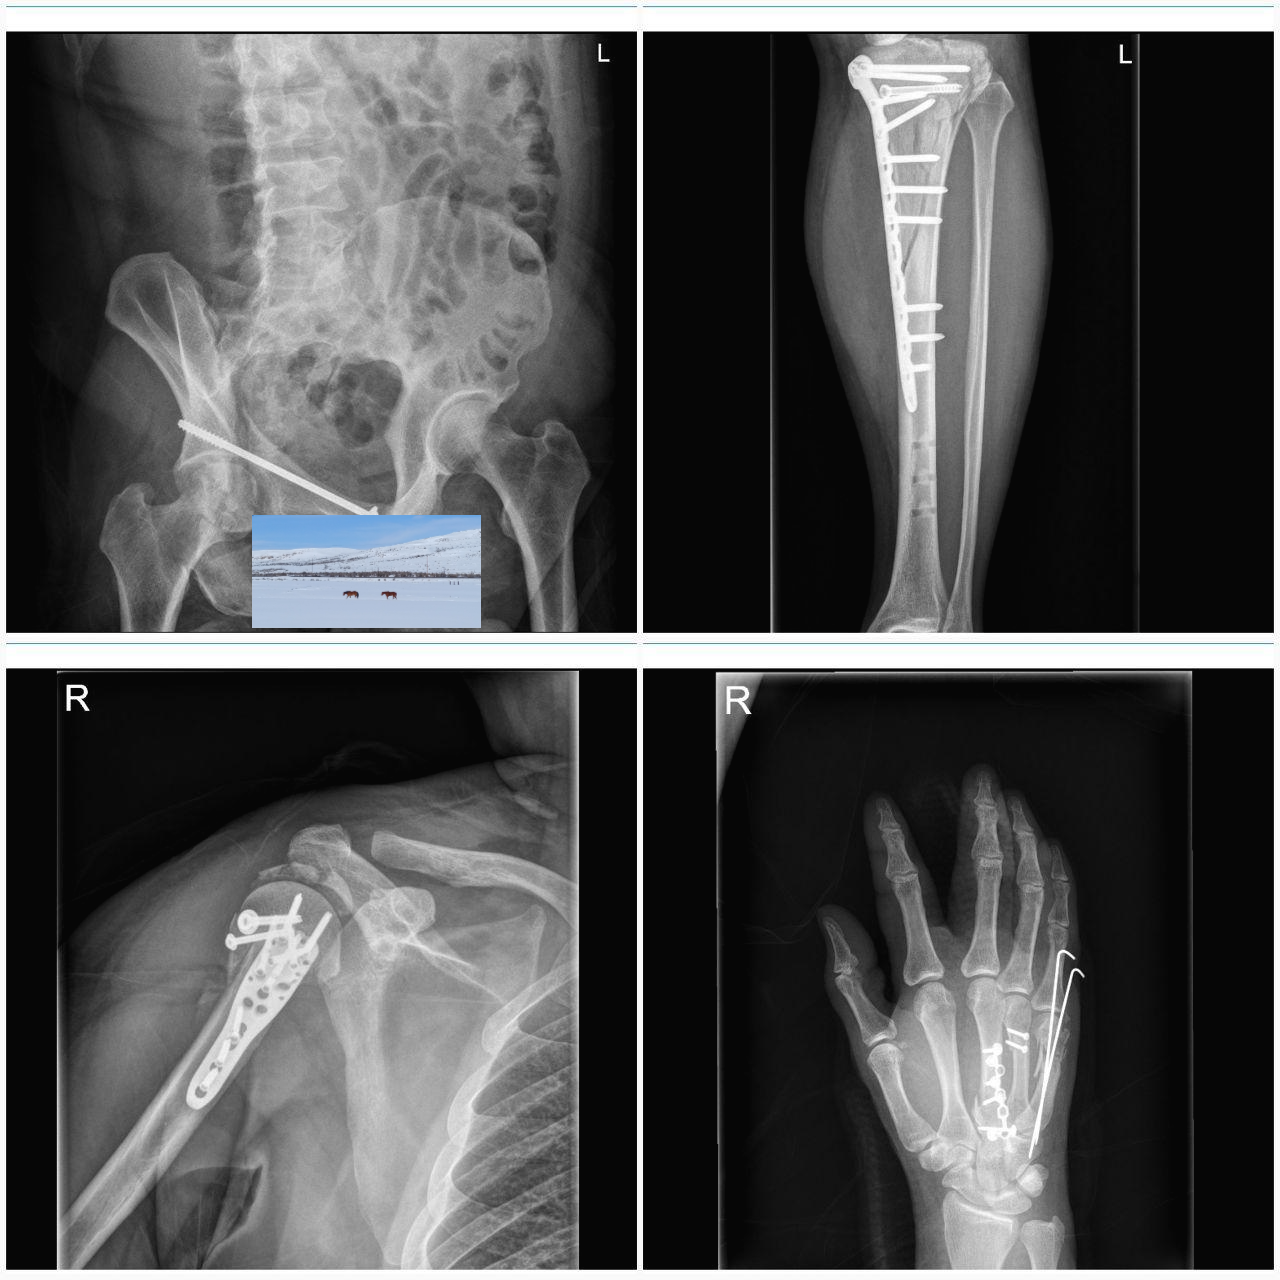

왼쪽 무릎 아래가 작살나서 핀을 박았어요.

골반이 두 군데가 깨졌어요.

어깨 절구가 산산조각이 났고 팔뼈도 부러졌어요.

코뼈와 안와골절이 있었고...

손등뼈와 손가락 골절도 있었어요.

병원 도착 후 한참이 지나서 응급수술로 뼈들을 대충 맞추고 제 기억이 없는 동안에 다시 다리 부기가 빠진 후 다시 수술을 해서 핀을 박았다더군요.

제 기억이 없는 동안의 2번의 수술.

기억이 돌아오고 일주일쯤 있다가 다시 골반뼈 하나 못 맞춘 것과 코뼈와 광대뼈, 안와 골절 수술을 받았어요.

다리뼈가 잘못 붙어서 다시 뼈를 잘라서 각도를 맞춘 뒤에 핀을 다시 박는 수술과 어깨와 손등의 핀만 제거합니다.